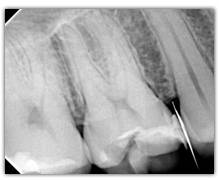

What represent the white, blue, red or black areas which can been seen on the tooth?

According to the pathologies of the tooth (destructured enamel, affected dentine, anfractuous fissure, presence of a crown…), the signal of fluorescence of the dentine will be different (weaker, darker, redder, absent…)

Why is the tooth green on the screen?

The spectrum of the signal of fluorescence (let’s call it "its color") is rather in the green when the dentine is healthy and red/dark when the dentine is infected.

When SOPROLIFE generates a red fluorescence in a fissure, it is either due to a caries or to organic deposits. In this case a cleaning (pounce bag, air abrasion linked to Na bicarbonate ) is advised only in the suspicious fissure in order to avoid a falser alert.